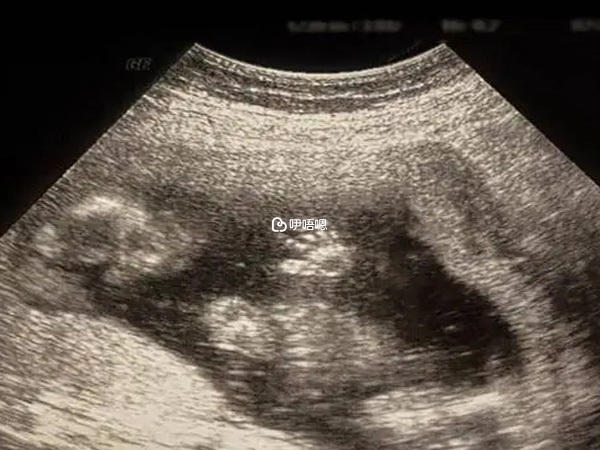

那幾天心情是緊張和複雜的,因為輸卵管通而欠暢的很容易宮外孕,所以每天都膽戰心驚的煎熬著,好在沒發現什麼異常,週一結果出來不方便請假去取結果,週二才拿到結果,我馬上就發給婦產科上班的醫生朋友看,諮詢她有沒有可能是宮外。她給我的回答是看結果沒有什麼問題,沒有異常不舒服就不用管,也安慰我說怎麼可能那麼容易宮外,讓我放下心再耐心等幾天再去醫院做B超確認。

一直煎熬著到了7周+才去醫院做了B超,確定是宮內後心理踏實多了。然後開始孕反,前期吐得很厲害,吃不下什麼東西,各種煎熬和難受,但是心裡面一直是欣喜的,這個寶寶來的太及時,也許是TA知道爸爸媽媽前期吃了很多苦,受了很多累,不想我們繼續遭罪。懷上寶寶後一路走來產檢各項指標一直都是順利通過,順風順水,我真的愛慘了肚子裡的寶寶。